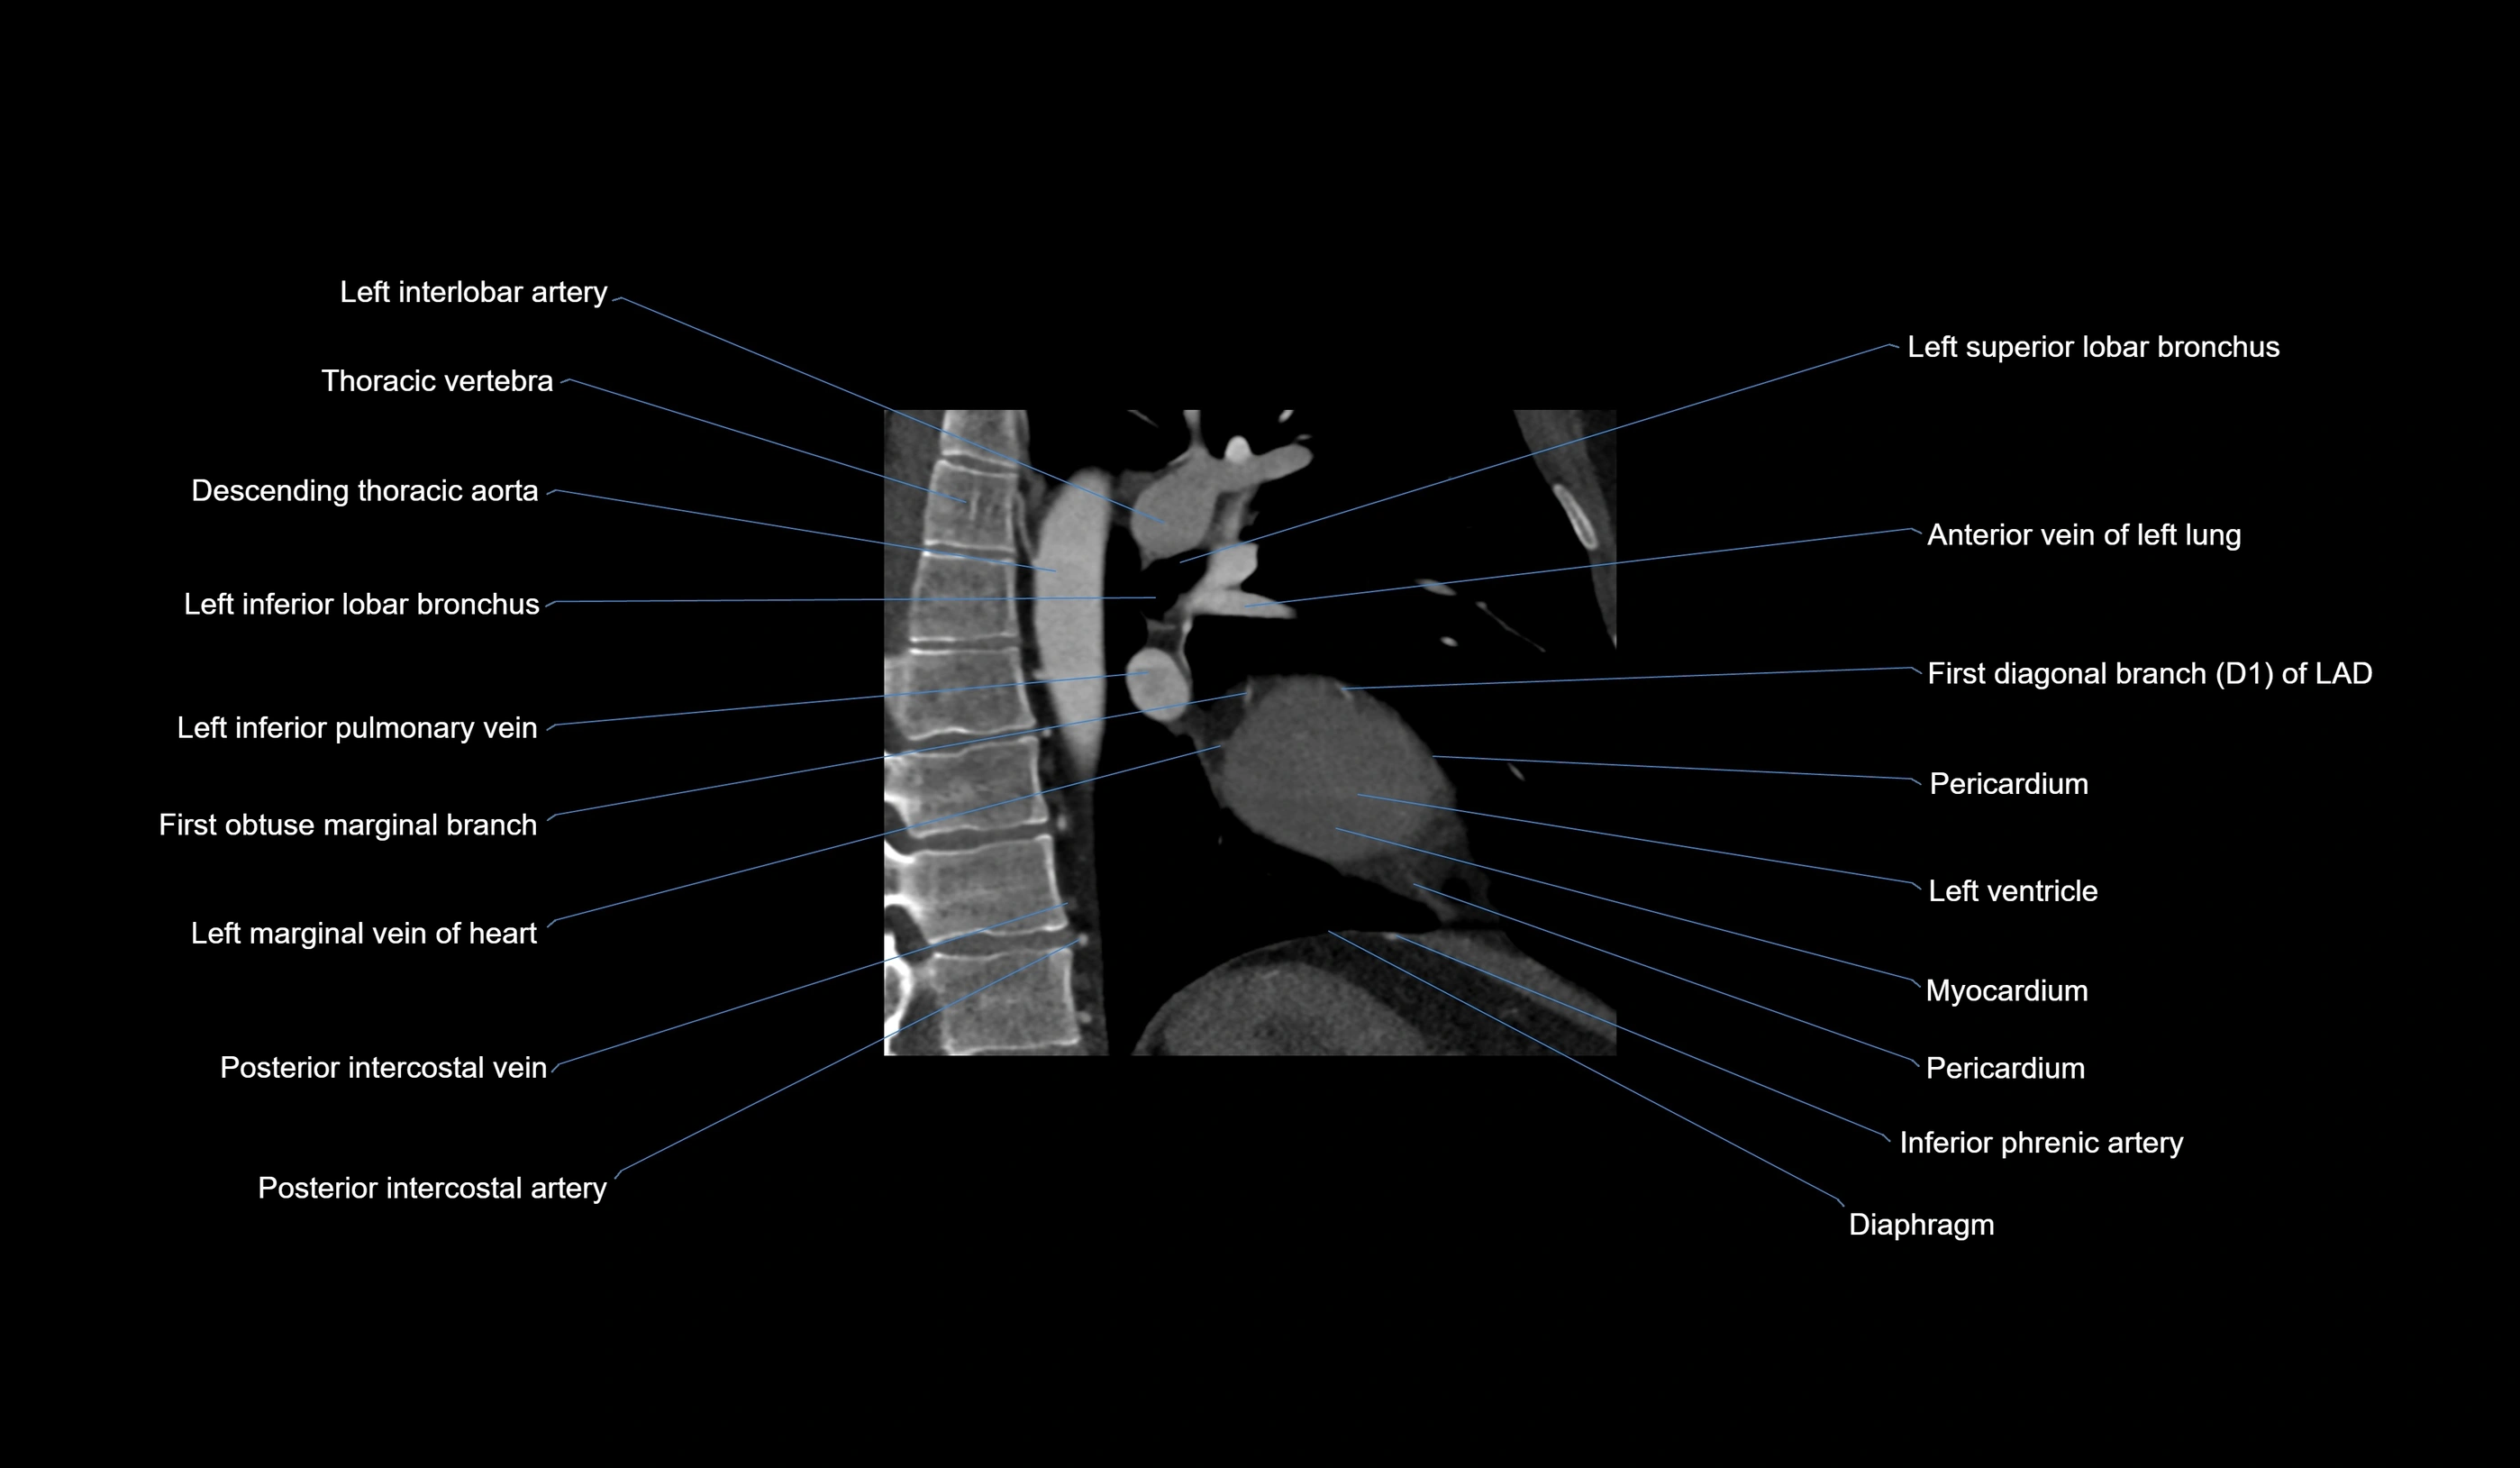

- Left interlobar artery

- Left inferior lobar bronchus

- Left inferior pulmonary vein

- First obtuse marginal branch

- Left marginal vein

- Anterior vein of left lung

- First diagonal branch (D1) of LAD

- Inferior phrenic artery

- Descending thoracic aorta

- Posterior intercostal veins

- Posterior intercostal arteries

- Left superior lobar bronchus